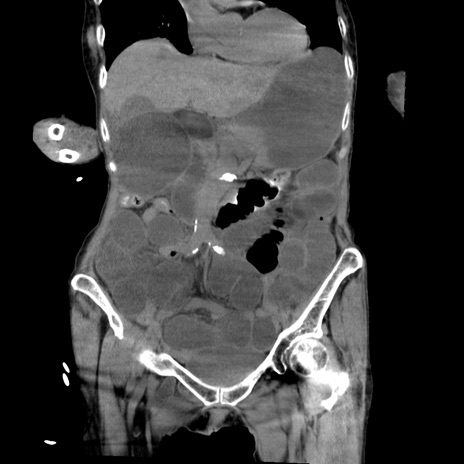

症例27(冠状断像)

【症例】80歳代女性

【主訴】嘔吐、腹痛

【現病歴】数時間前より嘔吐あり。心窩部痛出現し、徐々に右下腹痛あり。その後も数回嘔吐あり救急搬送となる。

【既往歴】左大腿骨頚部骨折手術

【身体所見】腹部は膨隆しているが軟らかく圧痛なし。腸雑音はやや亢進。

【データ】WBC 12000、CRP 19.05